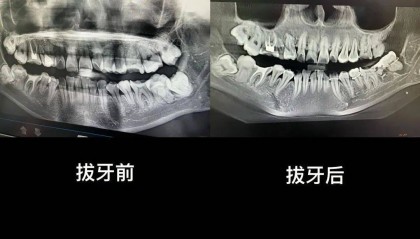

近日,安徽一名女子在网络自述“被安庆市立医院口腔科医生拔错牙齿并错误塞回”,后将个人简介改为“在市立...

女子疑因拔错牙又被塞回坠楼身亡,多方回应

近日,一位网友发文称自己34岁妹妹在安徽安庆市立医院口腔科门诊拔智齿,结果医生拔错一颗原生牙齿,并将...